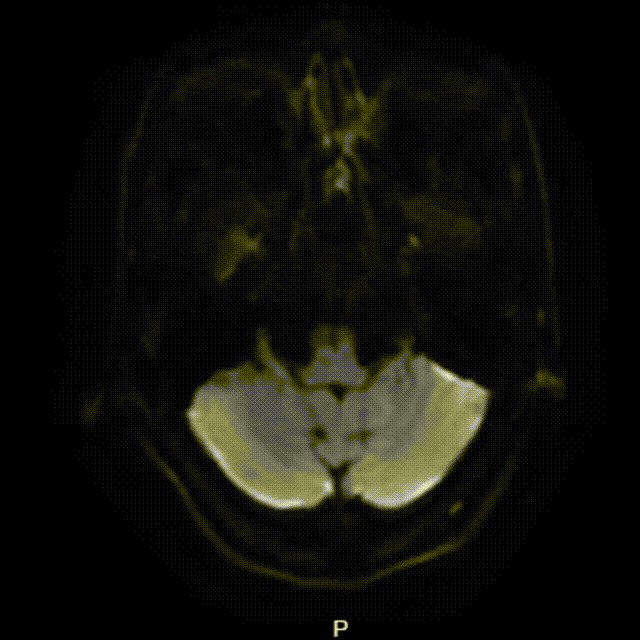

头部MRI+DWI提示:左侧大脑半球多发脑梗死,DWI像与T2 FLAIR像不匹配。